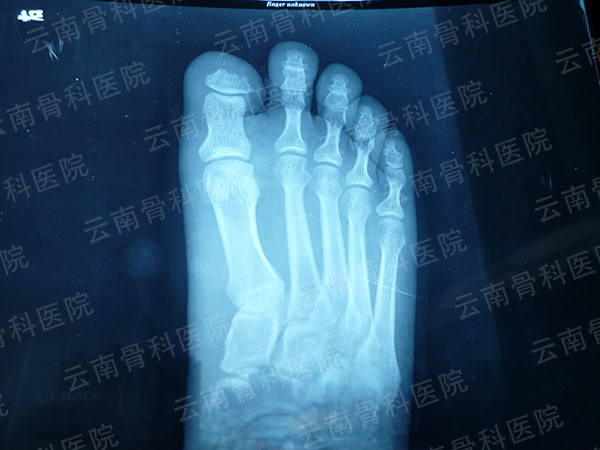

拇指Ⅱ度再造